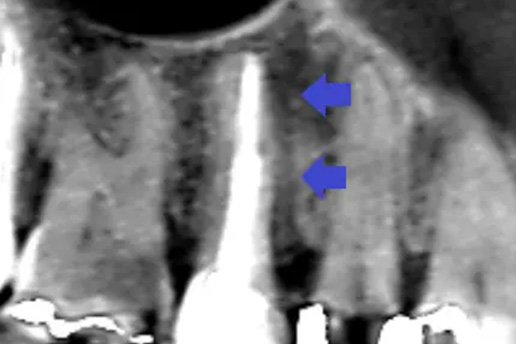

■歯周病の再生療法

歯周病が原因であごの骨が溶けてしまい歯がグラグラしていたケース。

再生療法で骨を再生させ抜歯せずに治療できた。